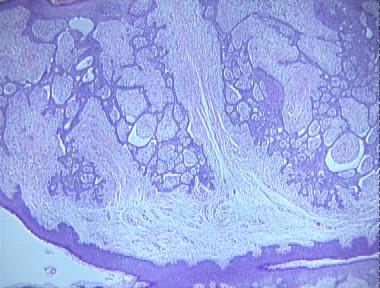

fibroepithelioma of Pinkus

Histologic Features